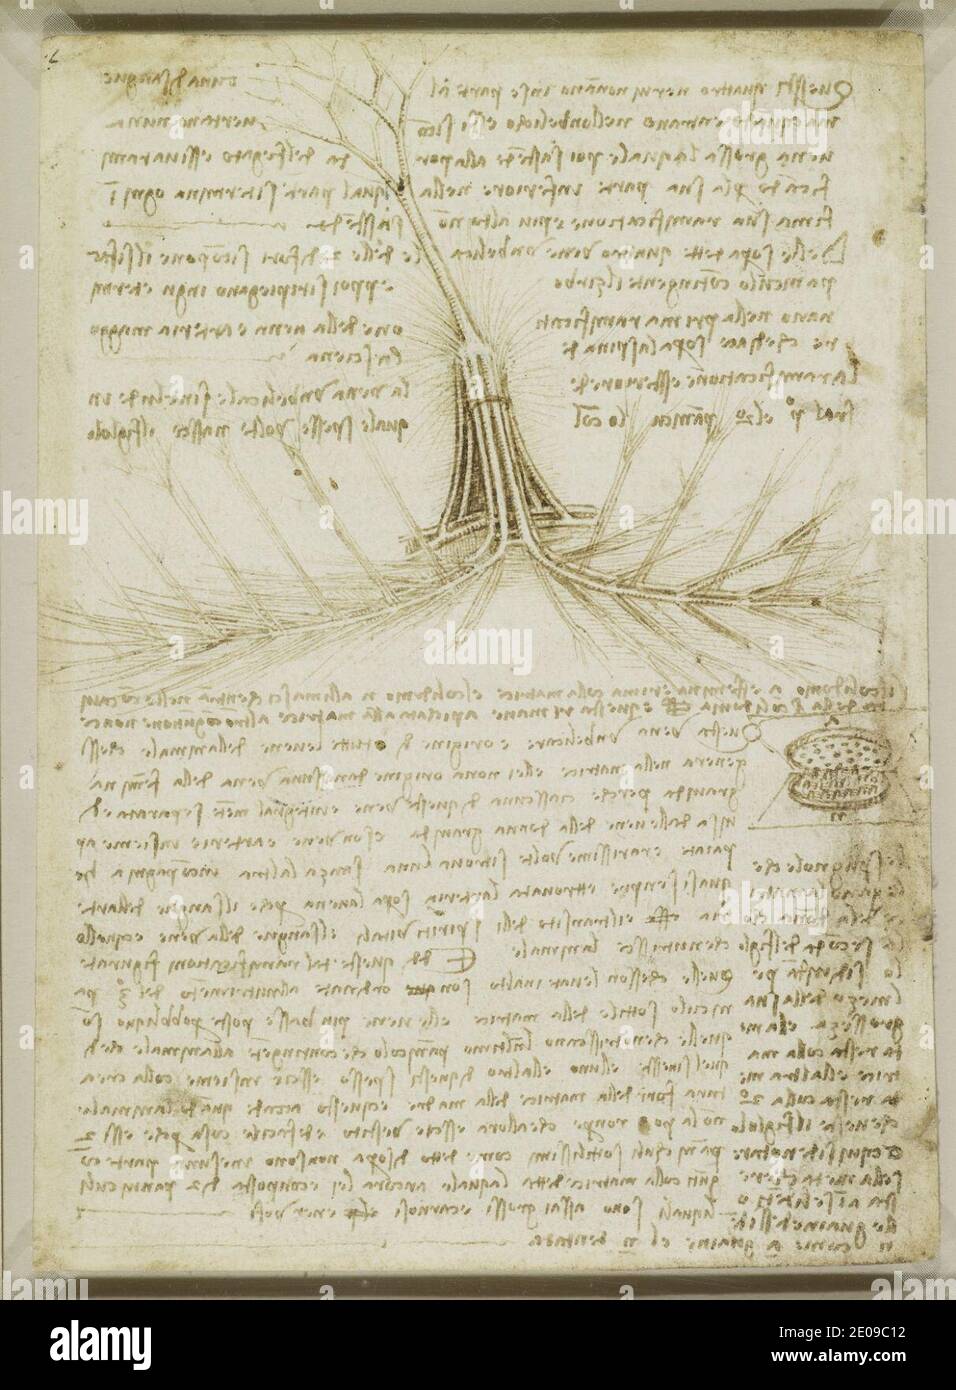

RM2E09C1Y–Leonardo da Vinci - Studien über die Blutversorgung der Gebärmutter und des Fötus, und Notizen über die Mechanik c.1510-13.